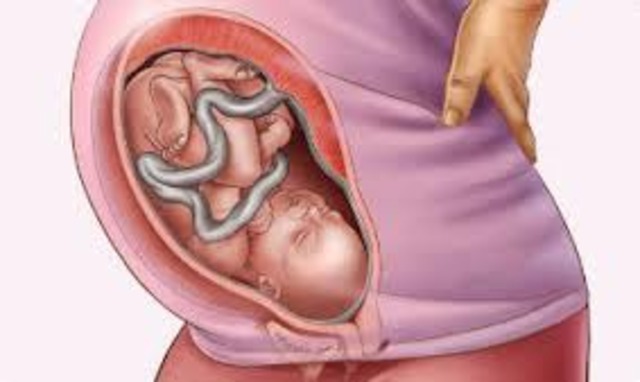

35 weeks pregnant

Your baby doesn't have much room to maneuver now that he's over 18 inches long and tips the scales at 5 1/4 pounds (pick up a honeydew melon). Because it's so snug in your womb, he isn't likely to be doing somersaults anymore, but the number of times he kicks should remain about the same. His kidneys are fully developed now, and his liver can process some waste products. Most of his basic physical development is now complete — he'll spend the next few weeks putting on weight.